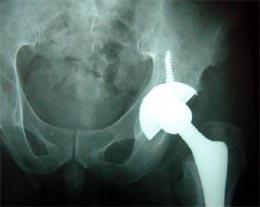

病例一

患者男性,52岁,左股骨颈骨折,曾经用空心钉和DHS固定,

两次手术均失败,股骨颈吸收,下肢短缩,疼痛,活动受限。

由于股骨近段两次手术均失败,导致股骨近段有骨质疏松骨缺损,

采用长柄的生物固定型股骨柄假体插入。

手术后X线片显示假体位置良好,双下肢恢复等长。患者功能恢复满意。